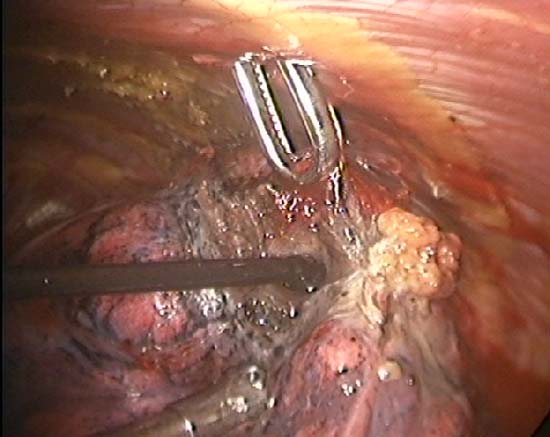

The TissueLink device does not perforate or cut into tissue (in contrast to conventional electrocautery). Instead, the surface of the tissue is painted with the device, which first coagulates and then shrinks the lung tissue (Figure 3). The surgeon then divides the coagulated tissue with scissors (Figure 4). Compared with conventional electrocautery, the TissueLink device usually leaves the resection bed more hemostatic and pneumostatic.

Slightly longer time is needed for resection using the TissueLink device. It is excellent in sealing small (1mm or less) bronchioles in the resection bed. The floating ball device should be applied directly over the bronchiole for one to two minutes to accomplish this. The TissueLink device, by nature of the technology, generates less smoke than conventional electrocautery. However, a small amount of steam is inevitable, and it is advisable to keep a sucker (a conventional Yankauer sucker works best) close to the surgical field, which also may be used to exert counter-traction on the lung tissue to facilitate dissection (Figure 5). As with all potential cancers, specimens should be placed in a bag before they are removed through a port site (Figure 6).